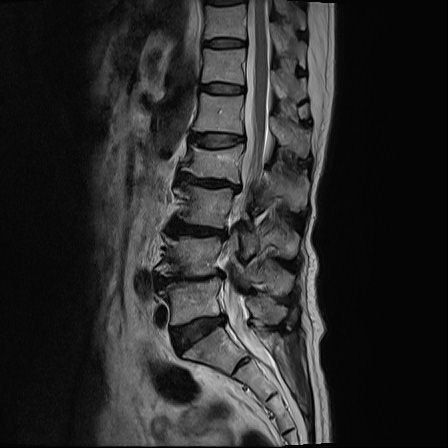

Ӵϲ ɿ ô ô 㸮 ٸ ̾ϴ. ϵ Ͻð ܻ 㸮 20⵿ ͽϴ. mri ˻ ɿ Ȳ ʹ ؼ Ȳ̶ ߽ϴ. ϻȰ ϰ 鼭 ½ϴ. ̴ ø鼭 Ͻô Ȳ ̷ ġ ص ȸ ϴ. δ Ҵµ, ù ȸԲ ˷ֽ ϰ β ϰ, ˷ֽ ü ƮĪ ϸ鼭 ȭǸ鼭 Ӵϲ ȸų ְ ǰ, β 鼭 ʴ β ؾϴ ŷο 1ϸ ijħ ڸ ǥ Ʈ ߽ϴ. ȸ ȭϽø鼭 Ϸ簡 ٸ ȸǽð 4ְ Ǿ Ǯ鼭 ¦ ҽϴ. ħ ȸ ȭϸ鼭 ڼ ü ƮĪ ϴ. ȥڼ Ͻʴϴ. ٳø鼭 ó Ͻ ʴϴ. ̾ ְ ̳ ߵ ʰ ϴ ȸԲ Ͻʴϴ. ʹ ϸ鼭 ϴ. Ȩ - ϱ ٴ Ȳ MRIԴϴ. |